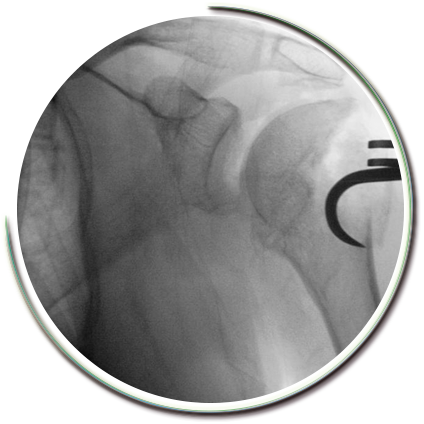

Parçalı kırıklarda kaynama sorunları ve işlev kaybı oluşmaması amacıyla sınırlı girişimsel cerrahi müdahale gerekebilmektedir. Kırık parçaları için çok kıymetli olan kanlanma bozulmadan (travmanın kendisi kanlanmayı yeterince etkileyebilir) kırık tespiti güçlü bir şekilde yapılabilmektedir. Kırık düzeltilmesi, açılan kas pencerelerinden yapılır. Parçaların tamamına hakim olabilmek amacıyla dikişler ve kilitli vidalı plaklar kullanılır. Kullanılan pencereler yerleştirilen plaklara göre oldukça küçük boyutlardadır. Pencerelerin bölgeden geçen sinirlere uygun mesafede olması gerekir.